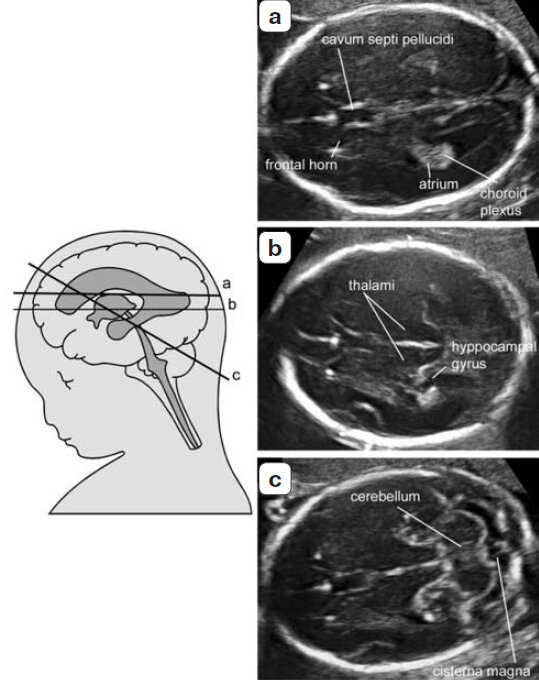

Два аксиальных сечения позволяют произвести осмотр основных структур мозга плода, на основании которых можно будет сделать вывод о нормальности его анатомии (17). Данные сечения получили название чрезжелудочковое и чрезмозжечковое сечения. Для проведения биометрии плода часто используется добавочное третье, так называемое чресталамическое сечение (рис. 1).

Рис. 1. Аксиальные сечения головки плода. (a) чрезжелудочковое сечение; (b) чресталамическое сечение; (c) чрезмозжечковое сечение.

Cavum septi pellucidi – полость прозрачной перегородки, frontal horn – передний рог, atrium – преддверие, choroid plexus – сосудистое сплетение, thalami – таламусы, hyppocampal gyrus – борозда гиппокампа, cerebellum – мозжечок, cisterna magna – большая цистерна.

В процессе базисного исследования должны быть осмотрены боковые желудочки, мозжечок, большая цистерна и полость прозрачной перегородки. Так же при осмотре данных сечений необходимо оценить форму головы плода и текстуру мозга (табл. 1).